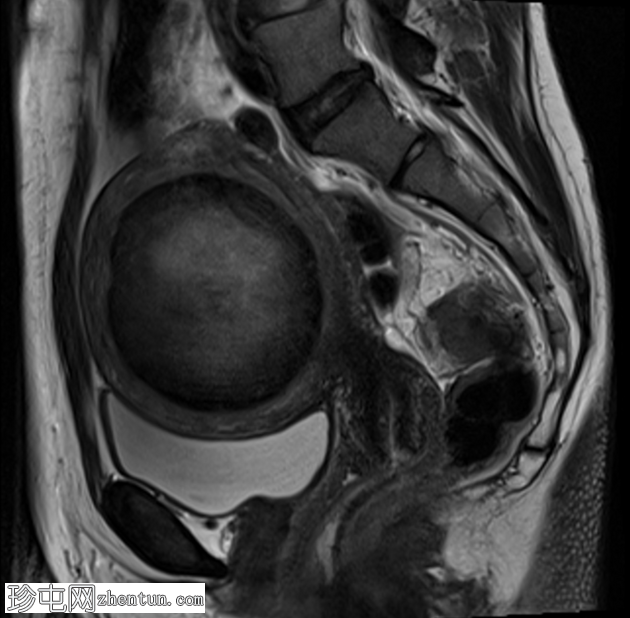

轴位T2加权像

脂肪抑制

子宫前壁可见一边界清晰的壁内病灶,大小约7.8 × 7 × 6.8 cm。脂肪抑制T1加权像呈弥漫性高信号,T2加权像呈高信号伴低信号环,无扩散受限及对比增强。

此外,可见一个2厘米的带蒂浆膜下肌瘤,以及较小的肌壁内和浆膜下肌瘤;所有肌瘤均呈均匀强化。

盆腔内可见少量游离液体,可能为生理性。